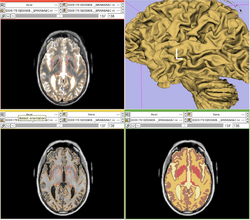

Our tool generates bias corrected images, fuzzy classification maps, and discrete segmentation labels. The tool has been used to automatically segment thousands of adult and toddler images from the University of North Carolina (UNC), and is also being used as a skull stripping mechanism for DTI processing at UNC and Utah. An example of the output of the tool is shown below.

Output of the segmentation plugin, showing the bias corrected image and the probabilities for white and gray matter.

ABC tool applied to TBI MRI data.

The ABC tool has been integrated into Slicer as an extension, and it can also be executed as a stand-alone application. Both versions are available for download through NITRC: http://www.nitrc.org/projects/abc .

Screen shot of the segmentation plugin in Slicer.